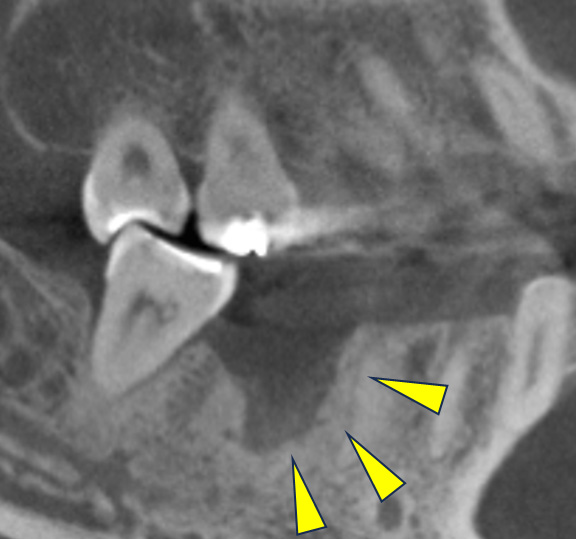

骨移植(人工骨+メッシュプレート)を行い、骨を造りました。

CT画像 -